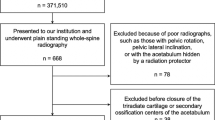

As part of the Norwegian prospective multi-centre study on Perthes’ disease, 425 patients were registered between 1996 and 2000 [8]. We analysed both the affected as well as the unaffected hips in all cases with unilateral involvement, age at onset 6 years or older and femoral head necrosis more than 50 % (n = 152). Radiographs were taken at diagnosis and at 1- and 5-year follow-up. The degree of femoral head necrosis was assessed according to the original Catterall classification [9]. We included radiographs classified as groups III and IV. Twenty-nine children were excluded due to inadequate exposure of the acetabular landmarks. Thus, 123 children (90 boys and 33 girls) with a mean age at the time of diagnosis of 7.5 years (range 6–13 years) were studied.

The radiographic phase was determined at the time of diagnosis according to Waldenström [10]. Sixty-three hips were in the initial phase (51 %), 48 were in the fragmentation phase (39 %), five were in the reossification phase (4 %) and seven hips had not been classified (6 %).

We applied the original lateral pillar classification of Herring et al. [11] in 110 patients at the fragmentation phase. Sixty hips were classified as lateral pillar type B (54.5 %) and 50 hips as lateral pillar type C (45.5 %). The femoral head cover was calculated as the percentage of the femoral head medial to Perkin’s line compared to the width of the femoral head, both measured parallel to Hilgenreiner’s line [4].

The children included in this study received either physiotherapy (n = 55), Scottish Rite orthosis (n = 26) or proximal femoral varus osteotomy (n = 71) [8], according to the choice of the local orthopaedic surgeons. The decision was based on surgeons’ preferences, treatment philosophy and local tradition. We combined patients treated with physiotherapy and orthosis into a non-operative treatment group.